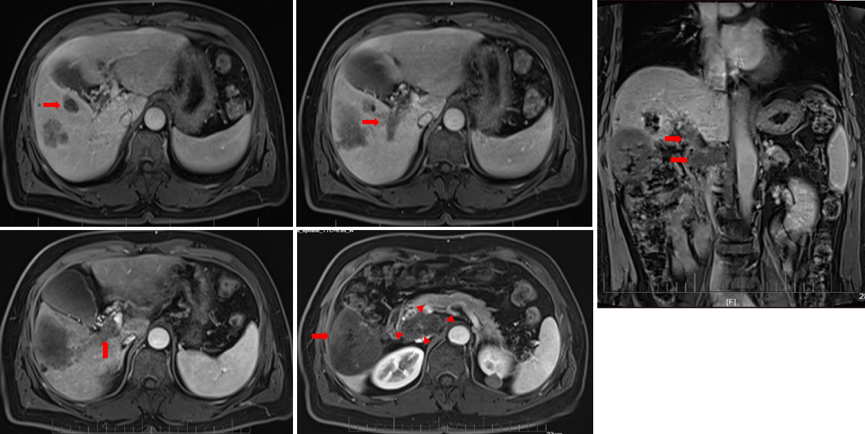

2021年3月13日、2021年4月19日、2021年6月23日复查MRI均提示维持治疗疗效稳定,总体评价仍为PR(图6)。

图6.2021年3月13日、2021年4月19日、2021年6月23日复查MR

2021年9月2日复查MRI显示,肝门及腹膜后淋巴结增大,腹膜后一转移病灶局部增大,评效PD(图7)。

图7.2021年9月2日复查MRI